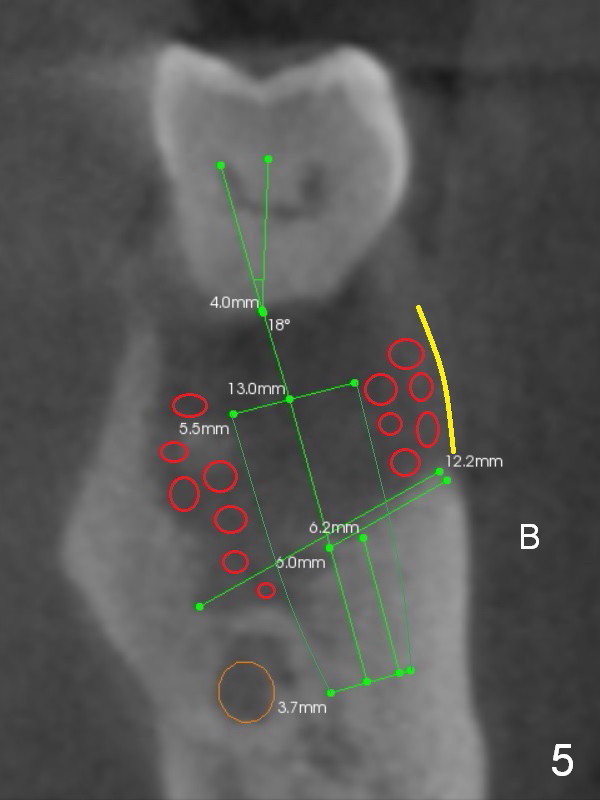

A 45-year-old man (SH) has periodontal (#3,9,19,23 (bone loss: Fig.1-3 *)) and orthodontic (#7,10 cross bite) problems, which he wants to solve at the same times. The tooth #19 is symptomatic (Fig.4,5). Infiltrate the buccal plate with 2% Xylocaine 1:50,000 Epinephrine and Septocaine (away from the Mental Foramen). After extraction and debridement, the socket is treated with Metronidazole. Osteotomy is initiated slightly buccal (B) to the middle of the socket bottom (Fig.5), using Sinus Master Kit drills (6 mm deep). After each drill, gently explore the lingual wall of the osteotomy with a fine curette or an explorer to determine whether the wall is perforated or not. Place a 5.5x13 mm implant (or short) between the buccal plate and the Inferior Alveolar Nerve (brown circle). If the torque is high, use the corresponding drill and tap. A 5.5 mm angled abutment will be used (15 or 25°, will arrive Monday morning). When X-ray is taken, the apex of the osteotomy should be superior to the upper border of the Inferior Alveolar Canal (Fig.4 U) and inferior to the Lower one (L). Bone graft is placed (Fig.4,5 red circles) after placement of PRF buccally (Fig.5 yellow curved line). If visibility is poor, make an incision and insert Epinephrine gauze under periosteum for hemostasis. Take photos when a 2 mm pilot drill in place to show the coronal end of the drill at the lingual cusp instead of the central fossa.